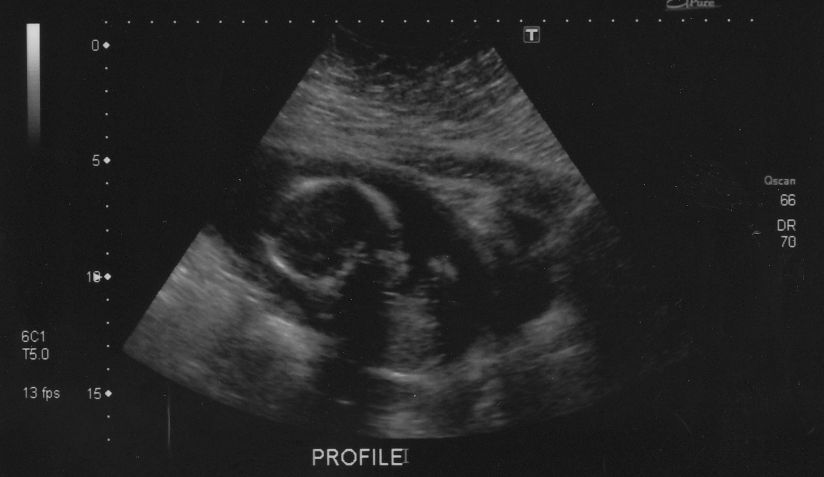

Danyoo wrote:The technician was having a hard time getting measurements because Cody was so active. "If I could just get baby to stop moving for a tenth of a second...I could measure his femur!"